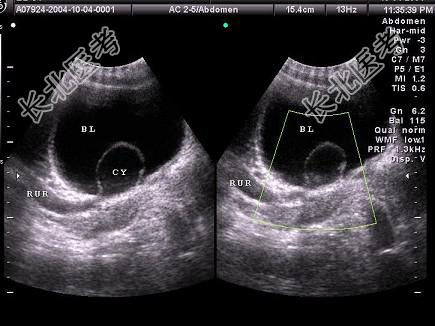

- 单项选择题女性,于膀胱输尿管位置见一囊性光团, 有规律收缩,增大。如图所示, 应要考虑为    (   )

A、膀胱肿瘤

B、输尿管囊肿

C、输尿管肿瘤

D、膀胱异物

E、膀胱憩室